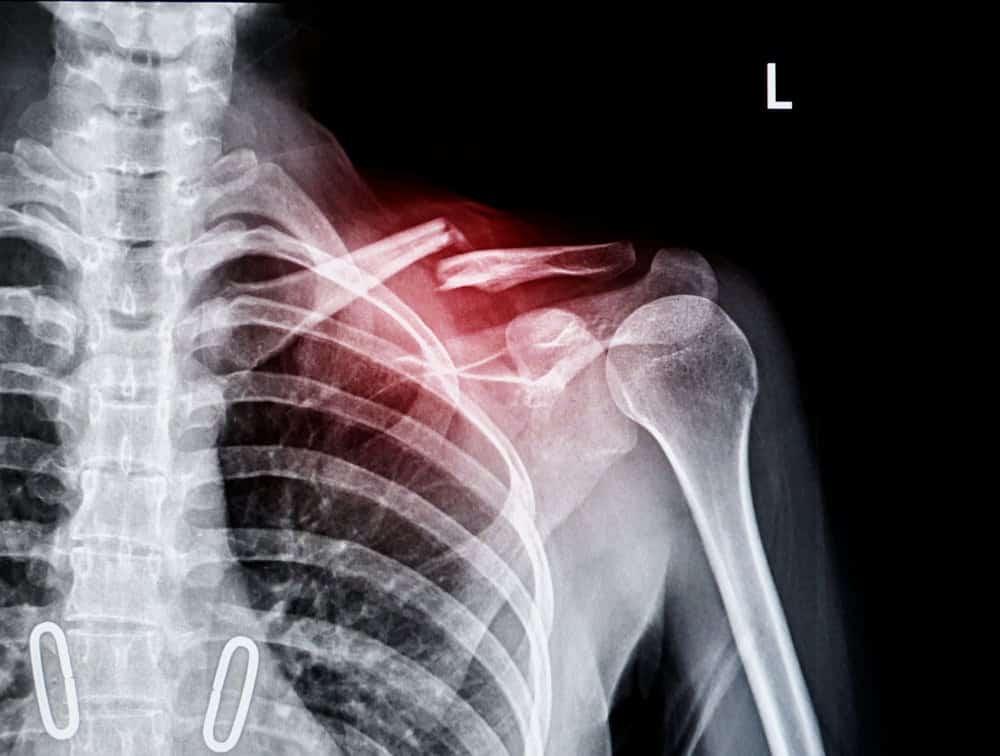

Khi đến bệnh viện, để chẩn đoán gãy xương chính xác thì bác sĩ sẽ tiến hành thăm khám và chụp X-quang hoặc CT để thu được hình ảnh chi tiết về tình trạng xương. Trên hình ảnh chẩn đoán, bác sĩ sẽ nhìn thấy vị trí gãy, đường gãy (ngang, chéo hoặc gãy xoắn), các di lệch, hình ảnh các mô mềm xung quanh. Một số ít trường hợp, người bệnh có thể được yêu cầu chụp MRI khi nghi ngờ có tổn thương mô sụn, khớp.